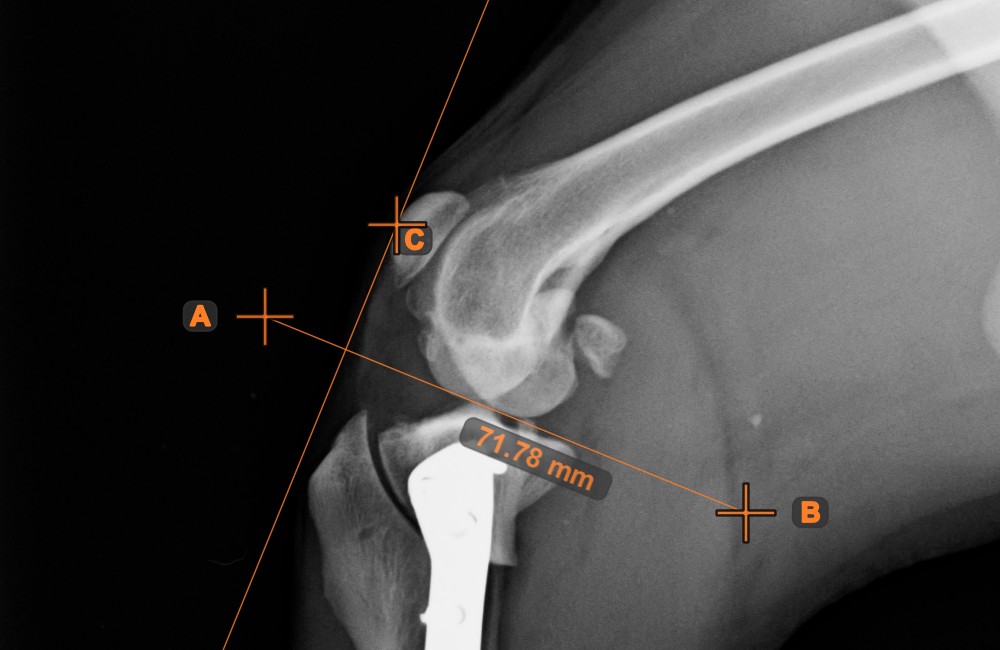

Vonal és pont távolsága¶

Mérje meg a távolságot egy vonal és a jelenet egy adott pontja között a Vonal és pont távolsága eszközzel.

Válassza ki az eszközt a bal oldali eszköztárból, és rendelje hozzá az egyik elérhető egérgombhoz. Kezdje el a mérést a jelenetben már meglévő vonal kiválasztásával. A mérés befejezéséhez helyezze el a kívánt pontot a jeleneten, vagy válasszon ki egy már meglévő pontot. A vonal és a pont közötti távolság automatikusan kiszámításra kerül.

Módosítsa a mérést bármelyik pont áthelyezésével a Elem kiválasztása/mozgatása eszközzel.